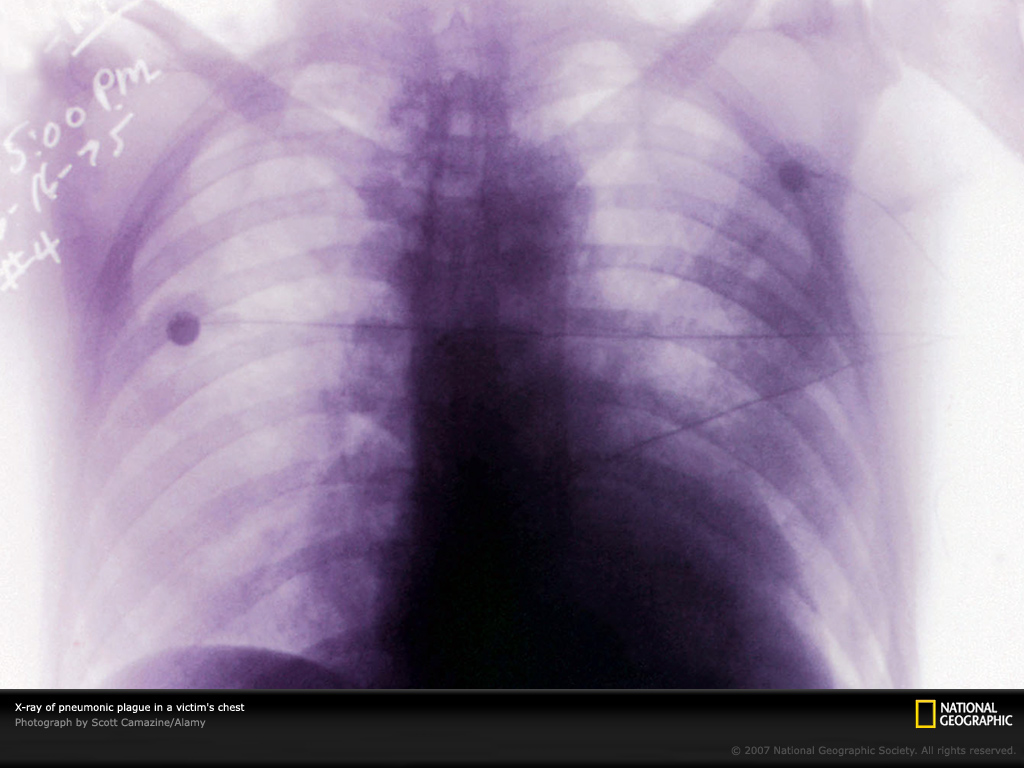

抗日战争时期,日本军国主义侵略我国,在东北研制、繁殖、各种渠道撒播鼠疫杆菌,用中国人做试验等令人发指,“国家地理杂志”在图片中作了介绍!。解放后,我国国内人间鼠疫已基本消灭,但自然疫源地依然存在,霸权主义者把鼠疫杆菌列为生物战剂之一,故防治鼠疫对我军国防和建设事业仍有非常重要意义。

下面请你观看11幅图片及说明词!Photo Gallery: Plague

Hell on Earth, the nightmare depicted by Flemish painter Pieter Bruegel in his mid-16th-century "The Triumph of Death" reflects the social upheaval and terror that followed plague, which devastated medieval Europe. Thought by most to be a scourge of the past, the bacteria of the plague still appears from time to time and has even been researched as a biological weapon by some countries.